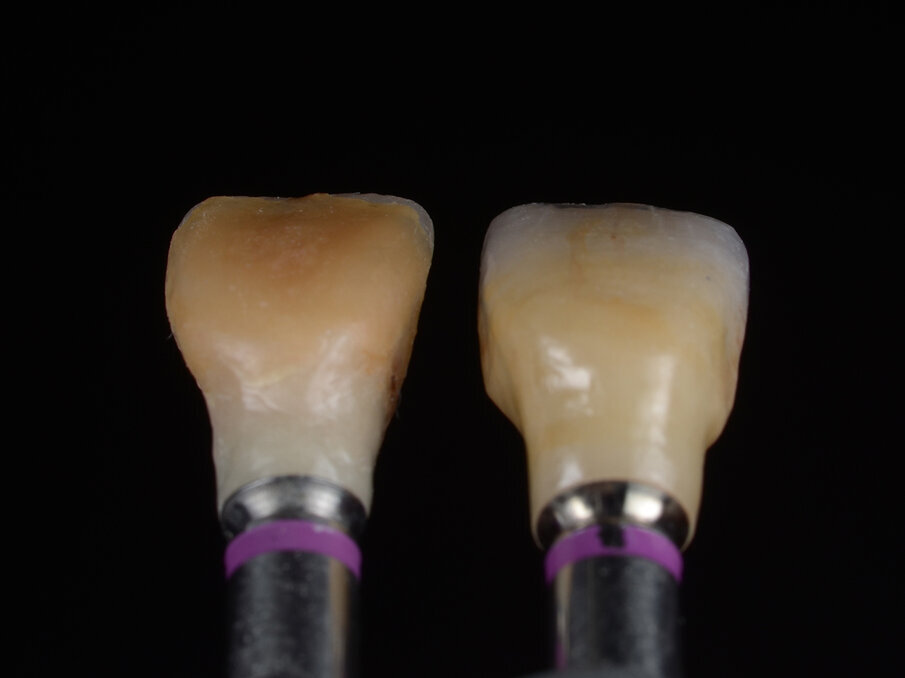

Un moncone in titanio per protesizzazione provvisoria (componente secondaria provvisoria - Straumann) viene modificato così da permettere un corretto alloggiamento della corona provvisoria e serrato manualmente. Protetto il canale della vite, il provvisorio viene forato in corrispondenza dell’accesso della vite protesica, posizionato in sede grazie alle alette e bloccato utilizzando del composito flow (G-aenial Universal flo - GC). Rimossa dal cavo orale, la corona provvisoria viene rifinita in laboratorio, completando il tragitto transmucoso in composito (Essentia Universal - GC) in modo tale da modellare un’area sotto-gengivale che sostenga i tessuti senza comprimerli. La riabilitazione provvisoria viene posizionata, avvitata e serrata a 20 N/cm. Il foro di accesso viene protetto con PTFE e sigillato con un’otturazione provvisoria (Telio CS onlay - Ivoclar), e i contatti occlusali vengono scaricati in modo tale da eliminare interferenze occlusali (Figg. 5, 6). Viene prescritta terapia farmacologica antibiotica, antidolorifica e sciacqui con collutorio a base di clorexidina digluconato. La paziente viene controllata a 7 giorni, 45 giorni e 90 giorni. A distanza di 3 mesi l’impianto viene considerato osteointegrato e i tessuti molli hanno raggiunto la loro stabilità. Il provvisorio viene quindi svitato (Fig. 7) e si procede tramite impronta ottica (Trios 3 - 3Shape) al trasferimento in laboratorio della posizione tridimensionale dell’impianto, della morfologia del tragitto transmucoso e della morfologia della componente sottogengivale della corona provvisoria (Figg. 8a, 9b). Una corona avvitata in zirconia con microstratificazione vestibolare viene confezionata come riabilitazione definitiva (Fig. 10). Superata la prova estetica, il manufatto viene consegnato e serrato a 35 N/cm. Il foro passante viene sigillato con PTFE e resina composita (G-aenial - GC) (Figg. 11, 12).

Fig. 10 - Valutazione post-operatoria: confronto tra corona provvisoria in resina e corona definitiva in ceramica.